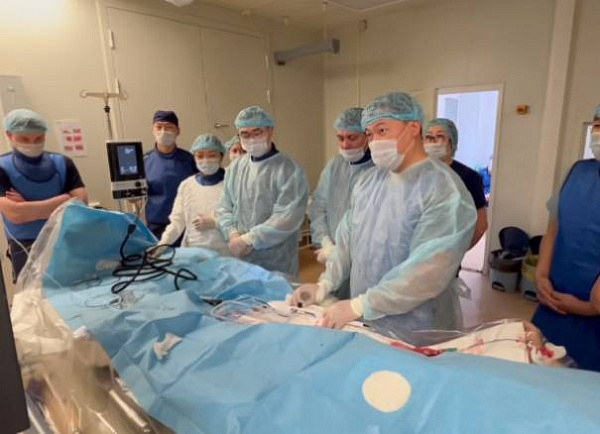

Уникальная операция в Бурятии: события и детали